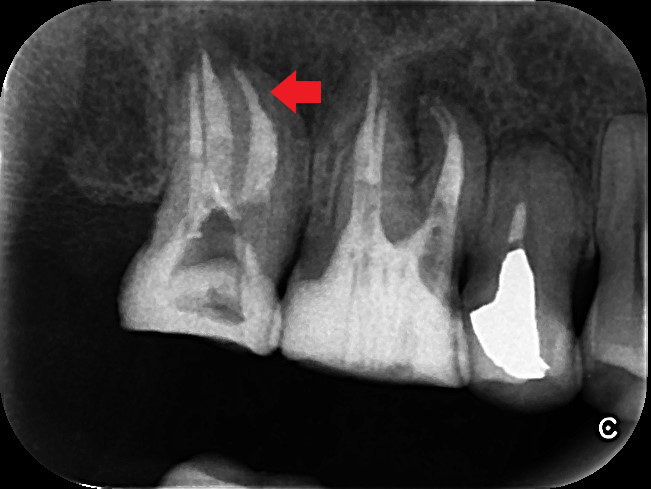

歯根の先に大きな膿があり、再根管治療が必要ですが破折ファイルが根管を塞いでいます。根管治療で膿を改善するためには、破折ファイルを除去し根管の殺菌・消毒が必要です。破折ファイルは除去が難しいケースもあり、必要に応じて外科的歯内療法を選択することもあります。本ケースは、手術なしで破折ファイルを除去し、再根管治療により大きな膿を改善しました。

破折ファイルがあり、根の先に膿がみられる場合は破折ファイル除去が必要になります。破折フィル除去には歯科用顕微鏡とCTスキャンがあると、安全にかつ確実な除去をしやすくなります。